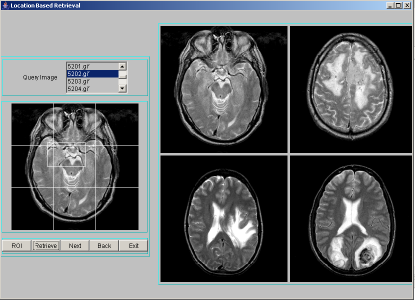

Location Based Indexing and Retrieval is performed by finding spatial location of a segmented region. The importance of location of objects is to identify the area of involvement of tumor like sensory or motor. The brain has unique areas for speech, hearing, visual, temperature regulation etc.. If the tumor which may not be centrally located, occurs at any particular area/location, then the corresponding organ gets affected. Hence location is an important feature to be indexed. To compute the location of a region, we divide the image space into 3x3 grid cells and number them 0-8 as shown in Figure 2. The region is likely to overlap number of cells in the image space. The index assigned is the cell number that is maximally covered by the region. A program segment to find location of a region is given in Table 5. We have considered an image size of 256x256 pixels in our work. The position of a region forms the location index. For each image in the database, segmentation procedure is applied to identify region-of-interest and describe segmented region by texture features: entropy, energy and contrast. Each location index stores region texture feature data along with the image object. For a query image, after finding the region-of-interest, the above mentioned texture features have to be computed and the location index is derived. Only those images that are stored at the location index matching those of the query index, are extracted as resultant target images for a given query image. These resultant images are sorted using Euclidean distance measure in the decreasing order of similarity against the query image and displayed four images at a time using JAVA-AWT based GUI. A few representative snapshots of location-based indexing and retrieval are shown in Figure 2.

![]() |